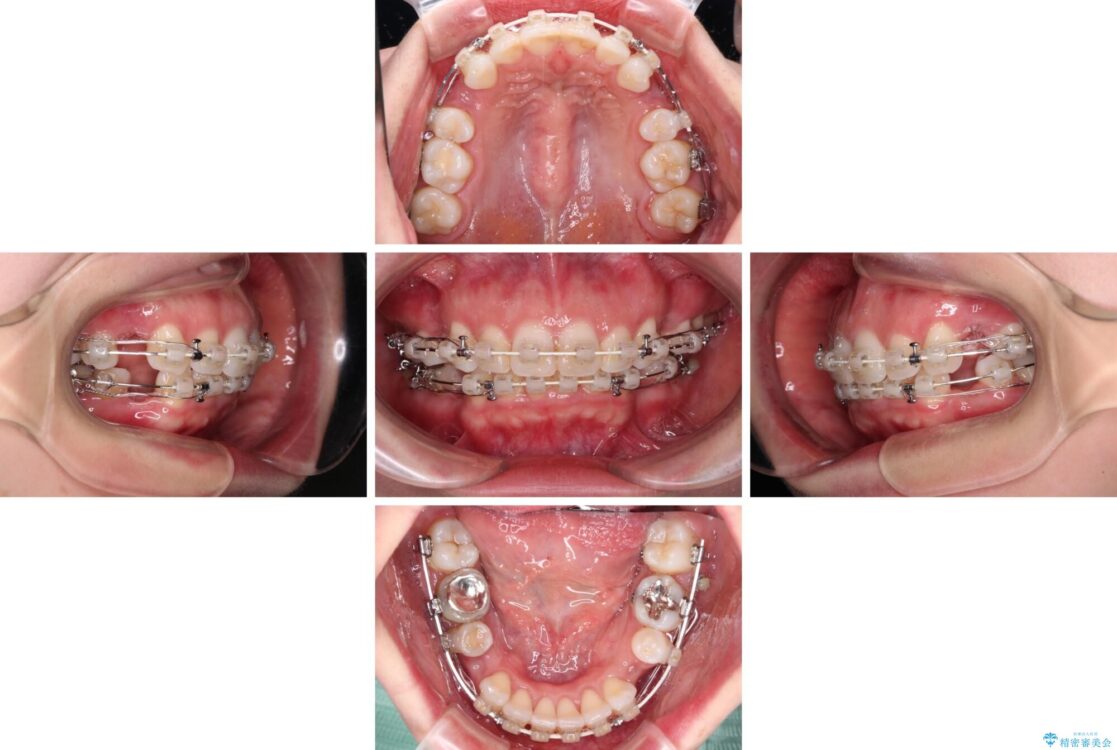

治療途中

• 【モニター】出っ歯と咬み合わせを改善 ワイヤー装置の抜歯矯正 治療途中画像

左下の大臼歯2本が顕著に舌側に傾斜しているため、まずは奥歯の咬み合わせを改善をし、その後上下左右の第1小臼歯4本を抜歯することで口元を引っ込めながら整えることとしました。

奥歯の咬み合わせ改善には1年ほどの期間と処置中の噛みにくさを強いることとなりましたが、抜歯後はスムーズに治療を完了させることができました。